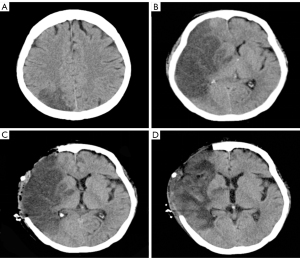

After admission, laboratory tests indicated random blood glucose (GLU) level of 12.74 mmol/L (normal value ≤11.1 mmol/L), base excess (BE) level of −3.4 mmol/L (normal range, −3 to +3 mmol/L), β-hydroxybutyric acid (β-Hb) level of 3.61 mmol/L (normal range, 0.02–0.27 mmol/L), white blood cell count (WBC) level of 17.44×109/L (normal range, 3.69–9.16/L), procalcitonin (PCT) level of 0.46 ng/mL (normal range, 0.00–0.05 ng/mL) and interleukin-6 (IL-6) level of 317 pg/mL (normal range, 0.00–7.00 ng/mL). Considering the presence of infection and diabetic ketoacidosis, the patient was given symptomatic treatment such as hypoglycemic therapy, ketone body lowering measures, and empirical anti-infection. A head computed tomography (CT) scan revealed a cerebral infarction in the right parietal lobe (Figure 1A). On hospital day 7 (2023-09-02), the patient’s mental status deteriorated to shallow coma. Follow-up cranial CT demonstrated progression of the cerebral infarction with concomitant cerebral herniation (Figure 1B). Cerebrospinal fluid (CSF) analysis showed leukocytosis (326×106/L; normal: 0–8 ×106/L) and elevated microalbumin (86.1 mg/dL; normal: 8.0–43.0 mg/dL). Concurrent metagenomic next-generation sequencing (mNGS) of CSF detected Rhizopus oryzae (76 sequences), confirming intracranial mucormycosis. Fungal meningitis (Rhizopus oryzae) complicated by cerebral infarction was diagnosed based on clinical and ancillary findings. Emergency right frontotemporal-parietal debridement with dural repair and intracranial pressure transducer placement was performed that day. The patient maintained stable vital signs intraoperatively, and postoperative cranial CT was obtained (Figure 1C). By September 9, 2023, surveillance cranial CT (Figure 1D) showed unchanged right hemispheric infarction extent with normalized density and resolved cerebral edema. On the second day of admission (2023-08-28), contrast-enhanced cranial MRI (Figure 2) demonstrated multiple right hemispheric infarcts. Contrast-enhanced orbital MRI (Figure 3) revealed soft tissue swelling in the right maxillofacial region and bilateral periorbital areas. After enhanced scanning, prominent enhancement was noted, suggesting infectious lesions and multiple groups of sinusitis. At the same time, CSF mNGS confirmed Rhizopus oryzae infection (as above). After identification of the pathogenic bacteria, liposomal amphotericin B (L-AMB) and posaconazole suspension were administered for antifungal treatment. Additionally, serial monitoring of infection markers—including complete blood count, PCT, and IL-6—showed progressive improvement (Figures 4,5).